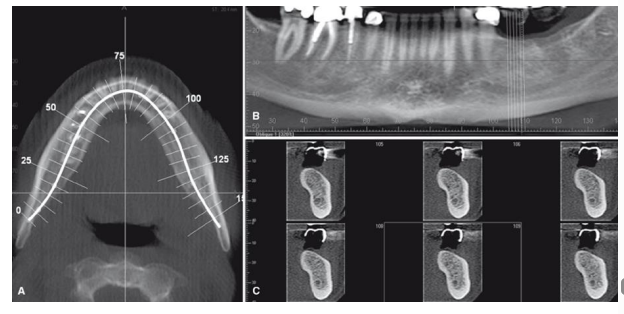

Analise as imagens a seguir, que são de um programa de reconstrução multiplanar, usadas para o

planejamento de implantes dentários (dental slice).

As imagens A, B e C, respectivamente, correspondem as radiografias: